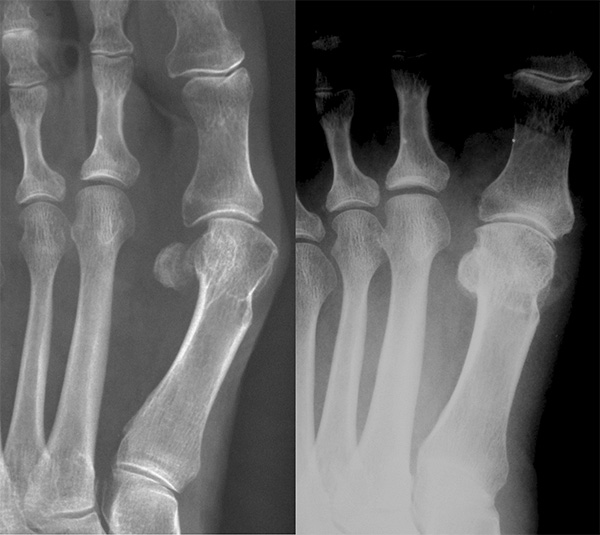

Die Rolle der Weichteilstrukturen in der Entwicklung des Hallux Valgus

Während der Entwicklung der Hallux Valgus-Deformität gleitet das MTK-1 nach medial ab und verliert dabei seine Position auf den Sesambeinen (Abbildung 2). Dies führt zwangsläufig zu einer Elongation der medialen ligamentären und kapsulären Strukturen und in Folge zu einer Verkürzung der lateral gelegenen Weichteile. Die Verkürzung des Lig. metatarsosesamoidale lat. korrespondiert mit der so genannten „Sesambeinluxation“, die auf dorsoplantaren Röntgenbildern oder in anatomischen Querschnitten (Abbildung 2) sichtbar wird und gleichzeitig mit einer Elongation des Lig. metatarsosesamoidale mediale einhergeht.

Es ist darauf hinzuweisen, dass der Sesambeinapparat generell seine Stellung in  Relation zum restlichen Vorfuß beibehält: die Distanz zwischen dem lateralen Sesambein und dem MTK-2 bleibt in der Regel gleich (entsprechend der unveränderten Länge des tiefen Querbandes [Lig. intermetatarseum transversum profundum]).